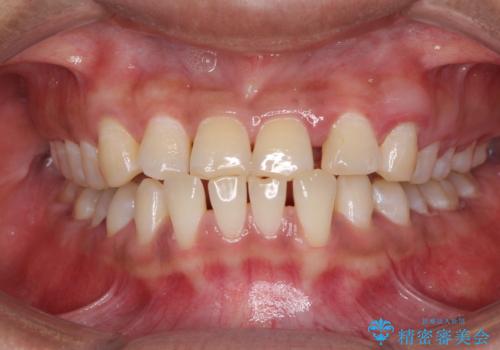

- 前歯の隙間と反対咬合を気にして来院された患者様です。

マウスピース矯正も提案しましたが、しっかりと使用する自信がないとのことで、ワイヤー装置により矯正治療を行うこととしました。